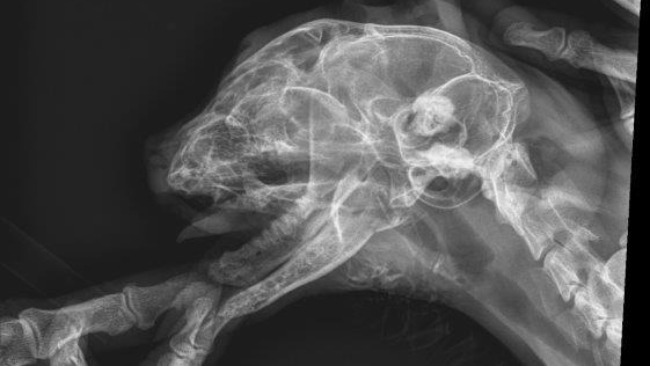

Po wielu telefonach znalazłam lekarza weterynarii - chirurga - który podjął się wykonania skomplikowanego zabiegu "naprawy" żuchwy. Koszt samej operacji to ok.2,5tys zł, pooperacyjny pobyt w szpitaliku, leki, potem usunięcie drutów - pewnie drugie tyle....

Kot dziś rano odebrany, późnym wieczorem dzwonił Pan Dr Oganiaczyk z informacją o przebiegi operacji.

Kot ma już dziób symetryczny, właściwie zamknięty - zdjęcia później.